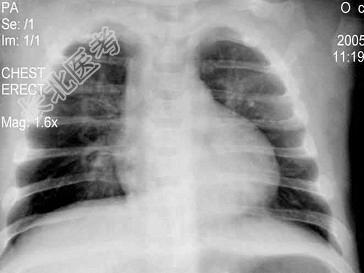

- 单项选择题6个月婴儿,持续高热8~10天, 精神萎靡,时有烦躁不安, 频繁咳嗽,喘憋。左下肺叩诊稍浊, 呼吸音降低,闻及小水泡音, 血白细胞8×109/L。胸部X线片示两肺纹理增多,可见大片状阴影, 伴有肺气肿,见图。最可能的诊断是 ( )

B、腺病毒性肺炎